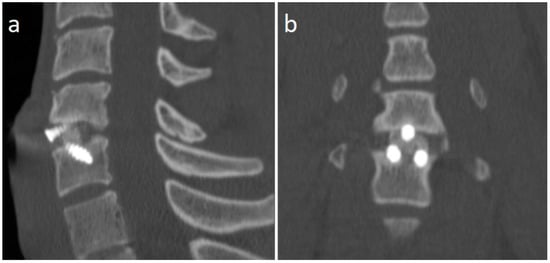

A 21 years-old male professional judoka started to feel neck pain radiating in the right C6 root dermatome with weakness in flexion-extension of the right forearm during a training activity. Due to the worsening of symptoms, the patient was suspended from the practice of judo. Moreover, he underwent a cervical spine MRI that showed the presence of C5-C6 disc herniation with C6 root compression and without spinal cord compression (Figure 2). After three months of conservative treatment (NSAIDs, steroids, physical therapy), surgical treatment was proposed. A standard C5-C6 ACDF with intraoperative neuromonitoring was performed with implantation of a stand-alone PEEK cage (CoRoent Small Interlock, NuVasive, San Diego, CA, USA) anchored with three titanium screws and packed with a biphasic calcium-phosphate bone graft substitute (AttraX Putty, NuVasive Inc., San Diego, CA, USA). The surgery was followed by a sudden relief from radicular pain, and the patient was discharged in two days. After a month of recovery, no motor or sensory deficits were detected at a neurosurgical follow-up visit. The CT of the cervical spine, three months after surgery, showed bone bridging as an initial sign of arthrodesis (Figure 3). In consideration of clinical and radiological outcomes, we recommended returning to training after 6 months and returning to competitive activities 7 months after surgery.

Figure 3.

CT scan sagittal (a) and coronal (b) images of the cervical spine 3 months after surgery, showing the formation of bone bridges as a sign of initial arthrodesis.

The overall rate of RTP after cervical spine surgery in martial art practitioners (87.5%) is substantially in concordance with results coming from studies conducted on other kinds of athletes. Hsu et al. [] included in their analysis 99 Nation Football League athletes; they reported a rate of 72% of RTP in surgically treated athletes. Maroon et al. [] report a higher RTP rate (86.7%) in 15 professional athletes that returned to practise their sport in 2–12 months. Mai et al. [] found an RTP rate of 74.3% in a sample of athletes belonging to four national leagues (NFL, MLB, NBA, NHL). Maroon proposes RTP criteria in a sample of football players and wrestlers []. These include solid arthrodesis and the absence of neurological deficits. The evidence of solid arthrodesis can be evaluated in plain radiograms showing the presence of bone bridging. In case of the absence of bone bridges or difficulty to ascertain it (for example, due to the material of the cage), the absence of movements in dynamic flexion-extension radiogram can be considered an indirect sign of arthrodesis. In our patient, a CT scan clearly demonstrated the presence of bone bridges as a sign of arthrodesis; we have not found other authors recommending this radiological exam before RTP. The absence of neurological deficit, both radiculopathy and myelopathy, can be assessed by the neurological exam. The need for postoperative MRI is controversial: while Maroon et al. recommends it in case of focal spine stenosis, Tempel et al. [] state that even the persistence of MRI T2-hyperintensity should not be considered an absolute contraindication to RTP in case of symptom-free athletes.